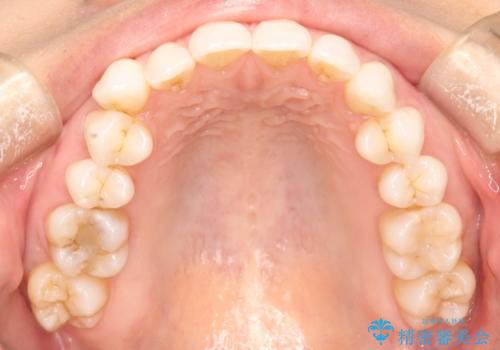

- 主訴:「右上犬歯を引っ込めて、歯並びをキレイにしたい」

右上の八重歯を気にされてご来院されました。結婚式を控えていたため挙式にまでに可能な限りキレイにしたいとのことでした。

右上の犬歯の歯茎は矯正前から退縮を起こしていましたが、矯正後もその退縮に関しては変化がありませんでした。今回は患者様が歯肉退縮に関しては治療をご希望ではありませんでしたが、当院ではこのように歯茎が下がり露出した根面を、歯茎を移植することでカバーし見た目を改善する手術を行っています。